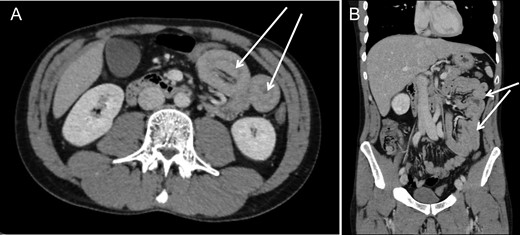

We present the case of a 30-year-old male patient who was admitted to our emergency department with a 24 h history of severe abdominal pain, diarrhea and vomiting. During clinical examination, the patient reported mentioned an episode with identical symptoms three months before that was treated conservatively at another institution. The patient’s past medical history included posttraumatic stress disorder and chronic consumption of cannabis via inhalation (10–15 joints a day). The pain intensity was so strong that the patient was observed by his girl-friend to sluice boiling water on his body. In the hospital at admission the patient was aggressive and endangered himself and others. The blood test demonstrated an increased leucocyte count with 16.88 G/l, but a normal C-reactive protein level with 0.1 mg/dl. At first, the patient was treated with lorazepame and olanzapine under clinical suspicion of acute psychosis related to his cannabis consumption. Due to further exacerbation of the pain, a CT scan was performed showing several small bowel intussusceptions in the left abdominal region (Fig. 1A and 1B). Because of the acute abdominal symptoms and the findings in the CT scan a diagnostic laparoscopy was performed. Intraoperatively numerous, at least ten, regions of jejuno-jejunal intussusceptions were found (Fig. 2A, Video 1). The intussuscepted jejunal segments were repositions by careful stretching of the small bowel. During examination of the affected bowel segments there was no evidence of a tumorous lesions or any other pathology (Fig. 2B). Only the intestinal content appeared thickened and pasty. Most interestingly severe atony of the whole small bowel was observed (Fig. 2A, Video 1). Because no ischemic leasions or other pathology was found, no intestinal resections deemed necessary and the operation was terminated. The patient developed no surgical complications, and had bowel movements after gastrografin application. Due to a good recovery, he was discharged on postoperative Day 2 with recommendation of adequate liquid intake and use of laxatives on demand.

Computed tomography revealed presence of several jejuno-jejunal intussusceptions in axial (A) and coronar (B) images.